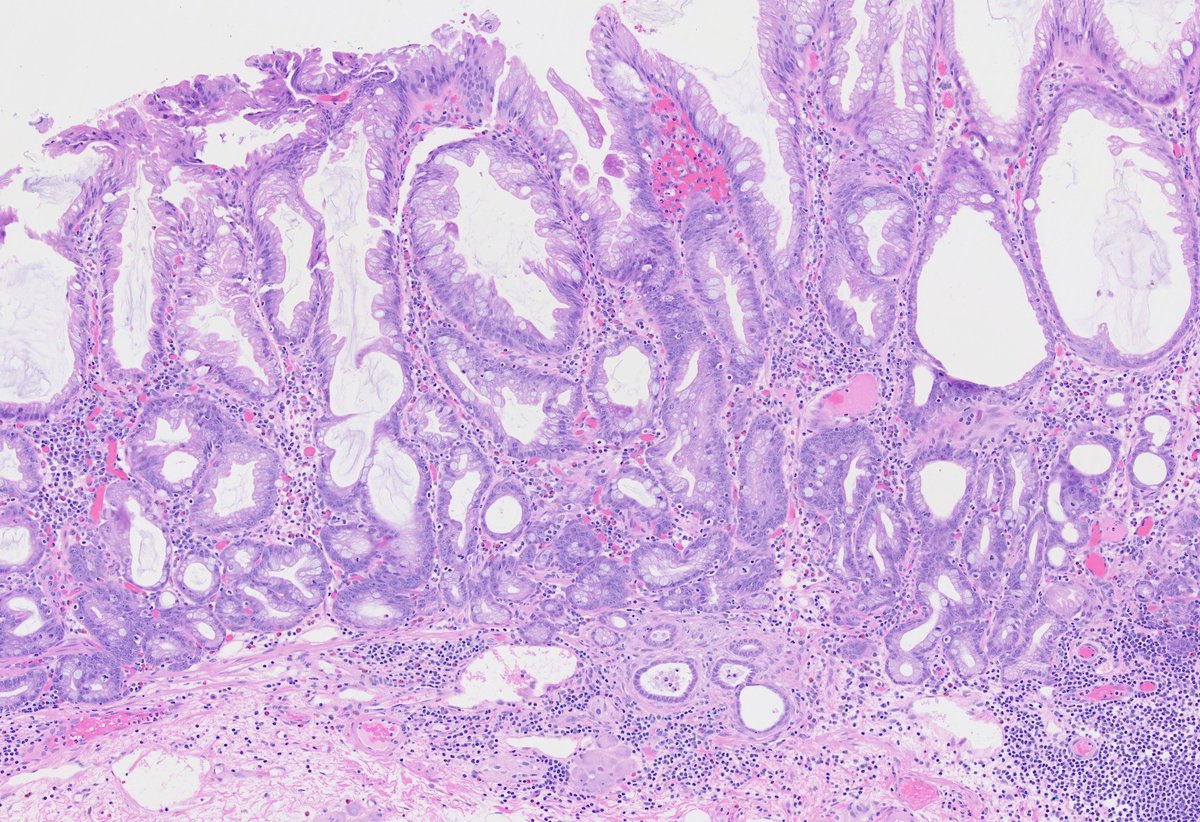

75-year-old male with a 4 cm mass in the lower pole of the right kidney. CA9 diffusely positive = CCRCC with a cute morphological appearance. #gupath GU Pathology Society (GUPS) International Society of Urological Pathology